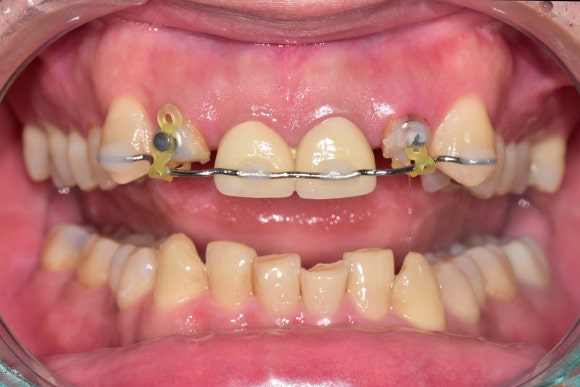

20250310

교정력을 가한지 2주 정도 되었습니다.

새싹이 나오듯이

1~2mm 정도 나오기 시작했습니다.

처음이 어렵지,

한 번 나오기 시작하면 쉽게 나옵니다.